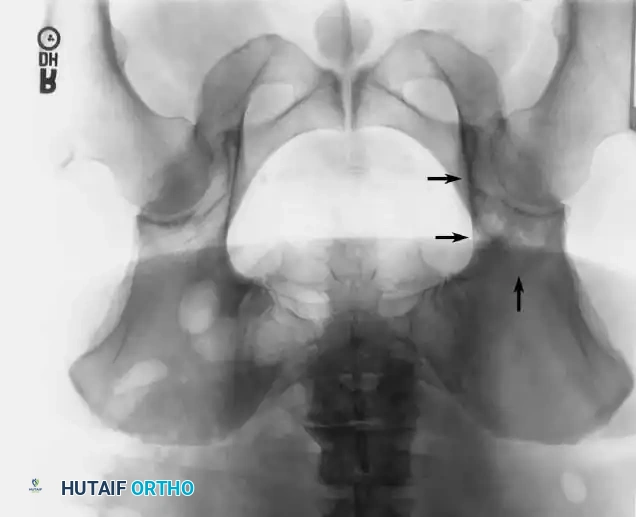

Intraoperative Imaging and Margin Assessment

Continuous intraoperative assessment using fluoroscopy and frozen section pathology is mandatory. The following images demonstrate various stages of complex upper extremity resections, allograft preparations, and prosthetic implantations across the humerus and elbow joint.